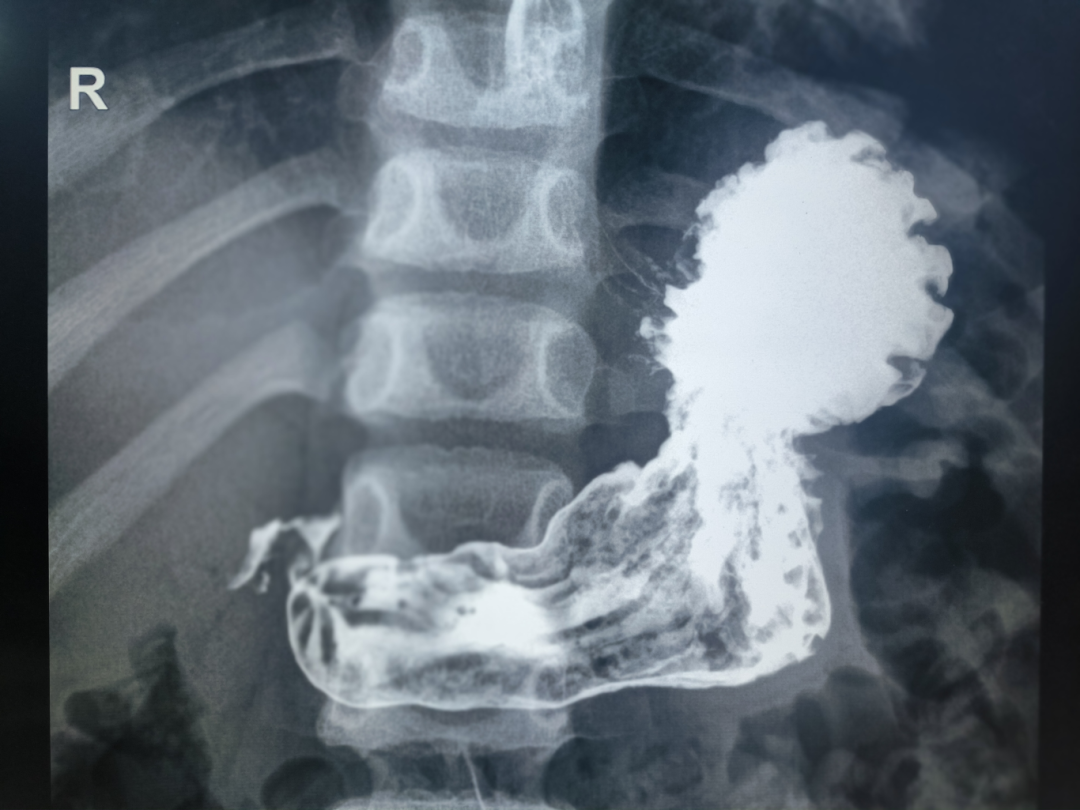

我们首先要了解一下上消化道造影就是通过口服对人体无害的造影剂,如医用硫酸钡,因为其密度大,不溶于水和脂质,也不溶于胃内其他物质,不会被胃肠道黏膜吸收,会直接被排出体外,在其经过食管、胃及十二指肠的过程中,由于人体各器官、组织的密度和厚度不同,显示出黑白的自然层次对比。利用X线检查动态观察、拍摄影片,记录过程,有助于观察食管、胃和十二指肠的轮廓、粘膜、蠕动状态、扩张度、通畅性等,判断胃肠道的器质性和某些功能性病变。

上消化道造影在儿童消化道疾病中起着至关重要的作用,有助于诊断和评估许多疾病,比如但不仅限于此:

1、幽门或高位肠梗阻;

2、食管裂孔疝;

3、怀疑或已知的胃炎或十二直肠炎;

4、膈疝或食管裂孔疝,包括复发性;

5、上消化道肿瘤;

6、消化道溃疡;

7、肠旋转不良。